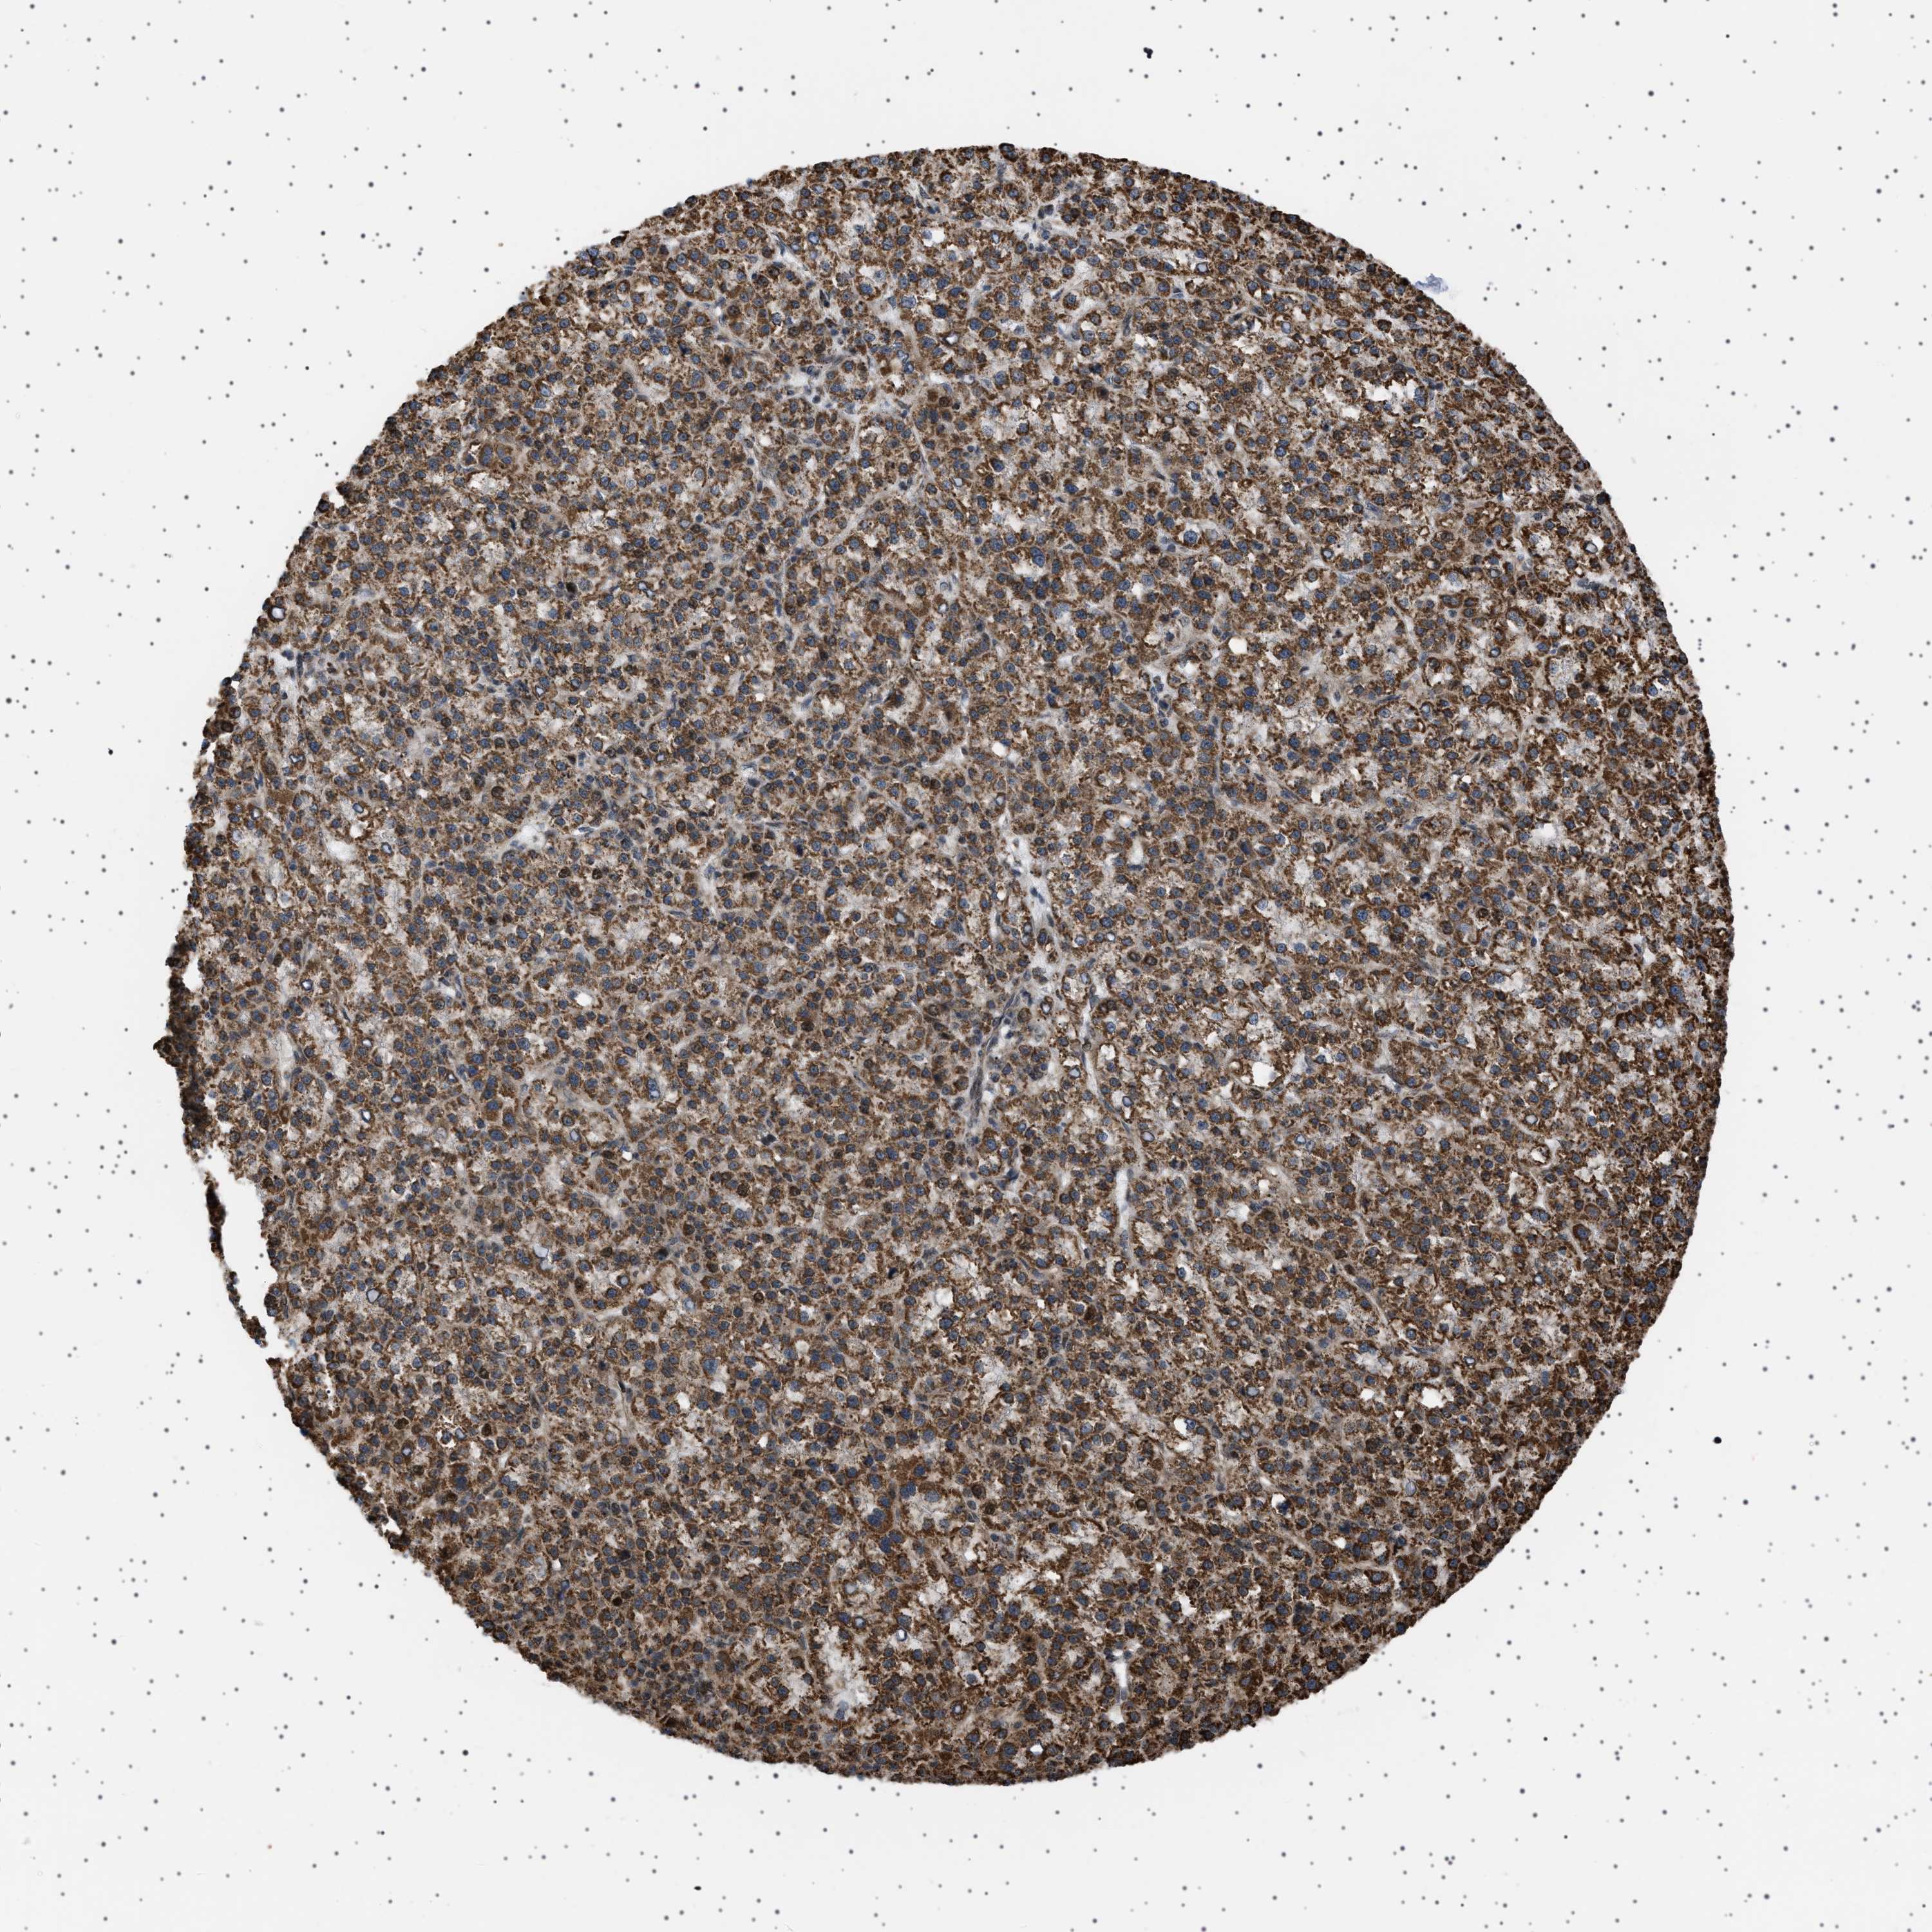

LIVER CANCER - Protein expressioni

A mouse-over function shows sample information and annotation data. Click on an image to view it in a full screen mode. Samples can be filtered based on level of antibody staining by selecting one or several of the following categories: high, medium, low and not detected. The assay and annotation is described here.

Note that samples used for immunohistochemistry by the Human Protein Atlas do not correspond to samples in the TCGA dataset.

Antibody stainingi

Antibody staining in the annotated cell types in the current human tissue is reported as not detected, low, medium, or high, based on conventional immunohistochemistry profiling in selected tissues. This score is based on the combination of the staining intensity and fraction of stained cells.

Each image is clickable and will lead to virtual microscopy that enables deeper exploration of all samples and also displays staining intensity scores, fraction scores and subcellular localization as well as patient and tissue information for each sample.

Antibody HPA017214

Staining

High

Medium

Low

Not detected

Intensity

Strong

Moderate

Weak

Negative

Quantity

>75%

75%-25%

<25%

None

Location

Nuclear

Cytoplasmic/membranous

Cytoplasmic/membranous,nuclear

Cholangiocarcinoma

Carcinoma, Hepatocellular, NOS